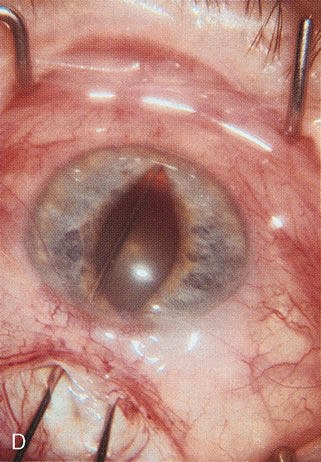

Fig. 3. Partial bleb failure following clear corneal phacoemulsification with foldable IOL. A. Preoperative bleb appearance prior to temporal lens extraction. Preoperative IOP was 12 mm Hg on no antiglaucoma medications. Time from 5-FU trabeculectomy surgery to lens extraction was one year. B. Bleb appearance 2 months after clear corneal cataract surgery with topical anesthesia. Following lens extraction, increased vascularity was noted along with decreased size of the filtering bleb. IOP increased to 20 mm Hg as early as 2 weeks after surgery, necessitating topical antiglaucoma therapy. C. High magnification view of bleb before lens extraction demonstrates diffuse pale bleb. D. High magnification view of bleb 2 months after surgery. There are vessels surrounding the nasal side of the bleb and the overall bleb size is smaller.

Fig. 7. Phacotrabeculectomy adjacent to a failed filter in cataractous eye. The ability to combine small-incision cataract extraction with trabeculectomy all through the same incision adjacent to the failed filter allows the surgeon to work in a familiar superior area. Avoiding incisions into the existing bleb decreases conjunctival buttonholes, hypotony, operating room time, and subconjunctival bleeding. A. Appearance of failed bleb with exposure of superior temporal quadrant gained with a corneal traction suture. B. Prepare a limbus-based conjunctival flap and a scleral flap. C. This bleb is at high risk to fail again justifying the need for MMC, 0.2 mg/cc applied on a pledget for 4 minutes. D. Insert the keratome and perform phacotrabeculectomy in the usual fashion.